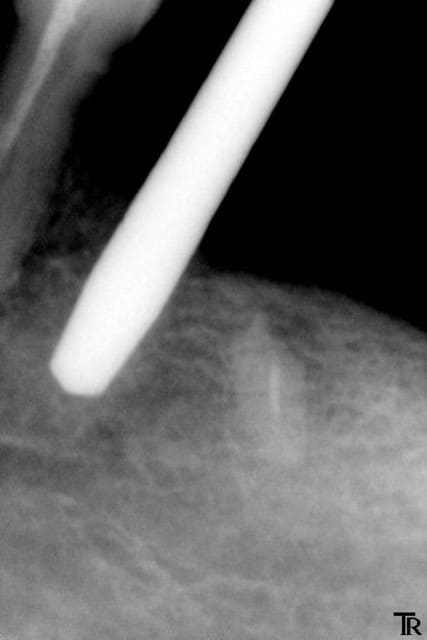

Je mets l’implant en place, et voilà ce que j’obtiens après la radio : l’implant qui aurait pu être mis plus profondément.

Trop stressé pour reprendre le forage. Trop peur de léser le nerf je laisse l’implant tel quel Le col en zircone de cet implant est en juxta osseux, mais l’os est très fin à ce niveau.

4 smilea en place vgbomh - Eugenol